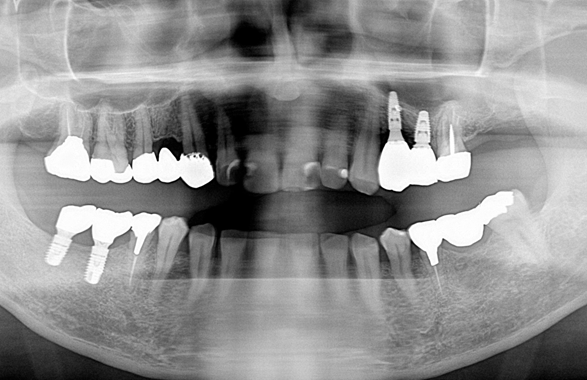

予定通りジルコニアクラウンにて、インプラント修復が行えました。

レントゲン写真でも理想的な位置

に埋入できました。

術前ではインプラントを埋入する骨組織はほとんど有りませんが、

術後完全に骨内に埋入出来ました。